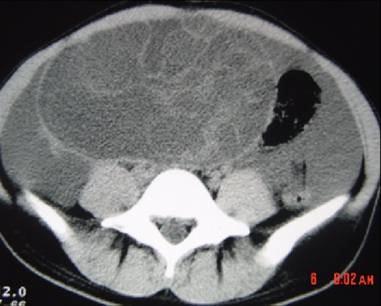

问题 40岁女性患者,下腹部隐痛、腹胀一年余,B超检查提示盆腔包块,行CT检查,如图,你认为最可能的答案是 ( )

选项 A、卵巢囊腺癌 B、卵巢浆液性囊腺瘤 C、卵巢囊肿 D、卵巢囊腺瘤 E、卵巢畸胎瘤

答案 D